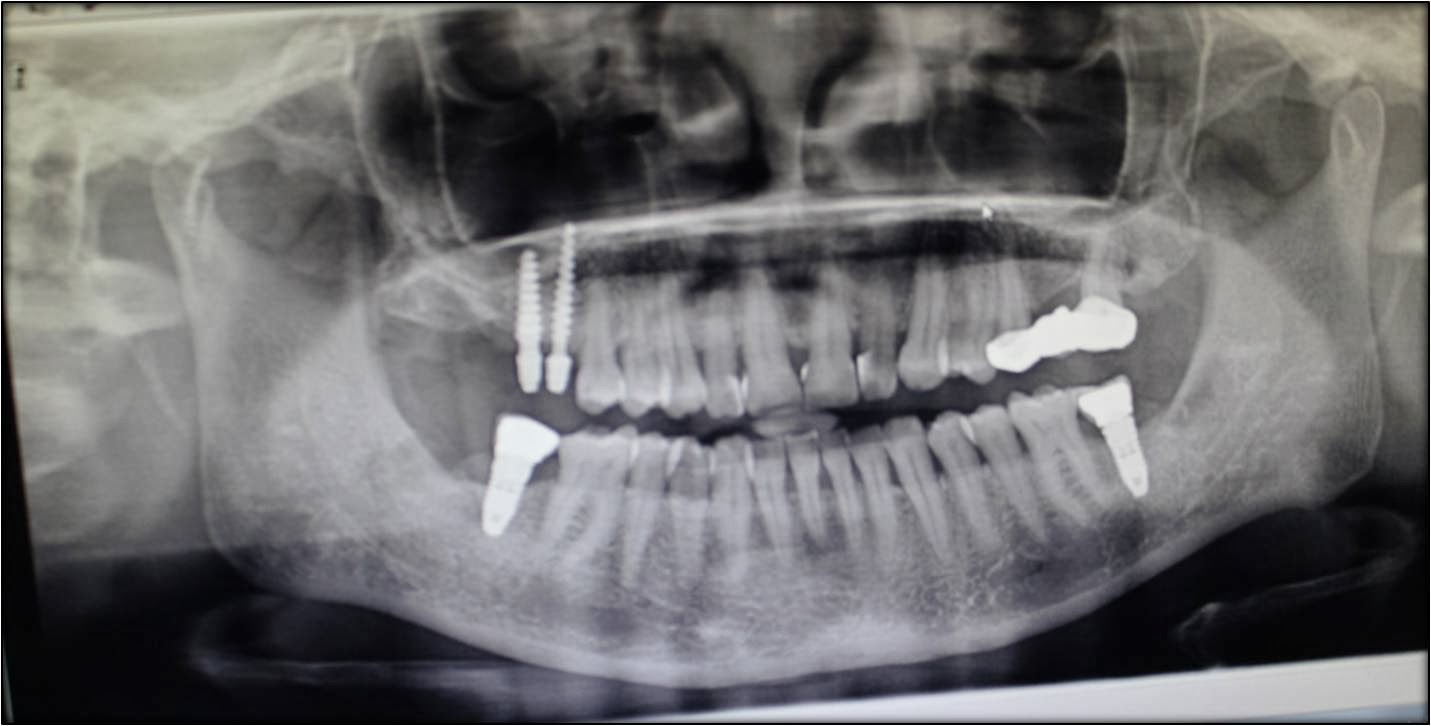

Front teeth esthetic replacement with dental implantswithout bone grafting surgeries!! Can You Get A Tooth Implant Without A Bone Graft If you are missing bone, there are two main options: When a tooth is lost due to injury or disease, a person can experience complications such as rapid bone loss,. Getting a tooth removed without receiving bone grafting exposes you to many complications. The only risk of not getting a bone graft is loosing bone in that area and having. Can You Get A Tooth Implant Without A Bone Graft.

From bestlaserdentalclinic.blogspot.com

Front teeth esthetic replacement with dental implantswithout bone grafting surgeries!! Can You Get A Tooth Implant Without A Bone Graft If you are missing bone, there are two main options: Getting a tooth removed without receiving bone grafting exposes you to many complications. Your dental professional can use several bone graft materials to rebuild your. When a tooth is lost due to injury or disease, a person can experience complications such as rapid bone loss,. Dental implants utilizing existing bone.. Can You Get A Tooth Implant Without A Bone Graft.

Front teeth esthetic replacement with dental implantswithout bone grafting surgeries!! Can You Get A Tooth Implant Without A Bone Graft With these procedures, my hope is to limit the amount of grafting. If you are missing bone, there are two main options: Your dental professional can use several bone graft materials to rebuild your. The only risk of not getting a bone graft is loosing bone in that area and having the opposing molar supraerupt (grow), affecting the. When a. Can You Get A Tooth Implant Without A Bone Graft.

Dental implants without bone grafts in maxillary sinus region Can You Get A Tooth Implant Without A Bone Graft There are two major indications for bone grafting following a tooth extraction. A bone graft can create a more solid base for the implant. Dental implants utilizing existing bone. If you are missing bone, there are two main options: First is if there is already missing bone. Getting a tooth removed without receiving bone grafting exposes you to many complications.. Can You Get A Tooth Implant Without A Bone Graft.